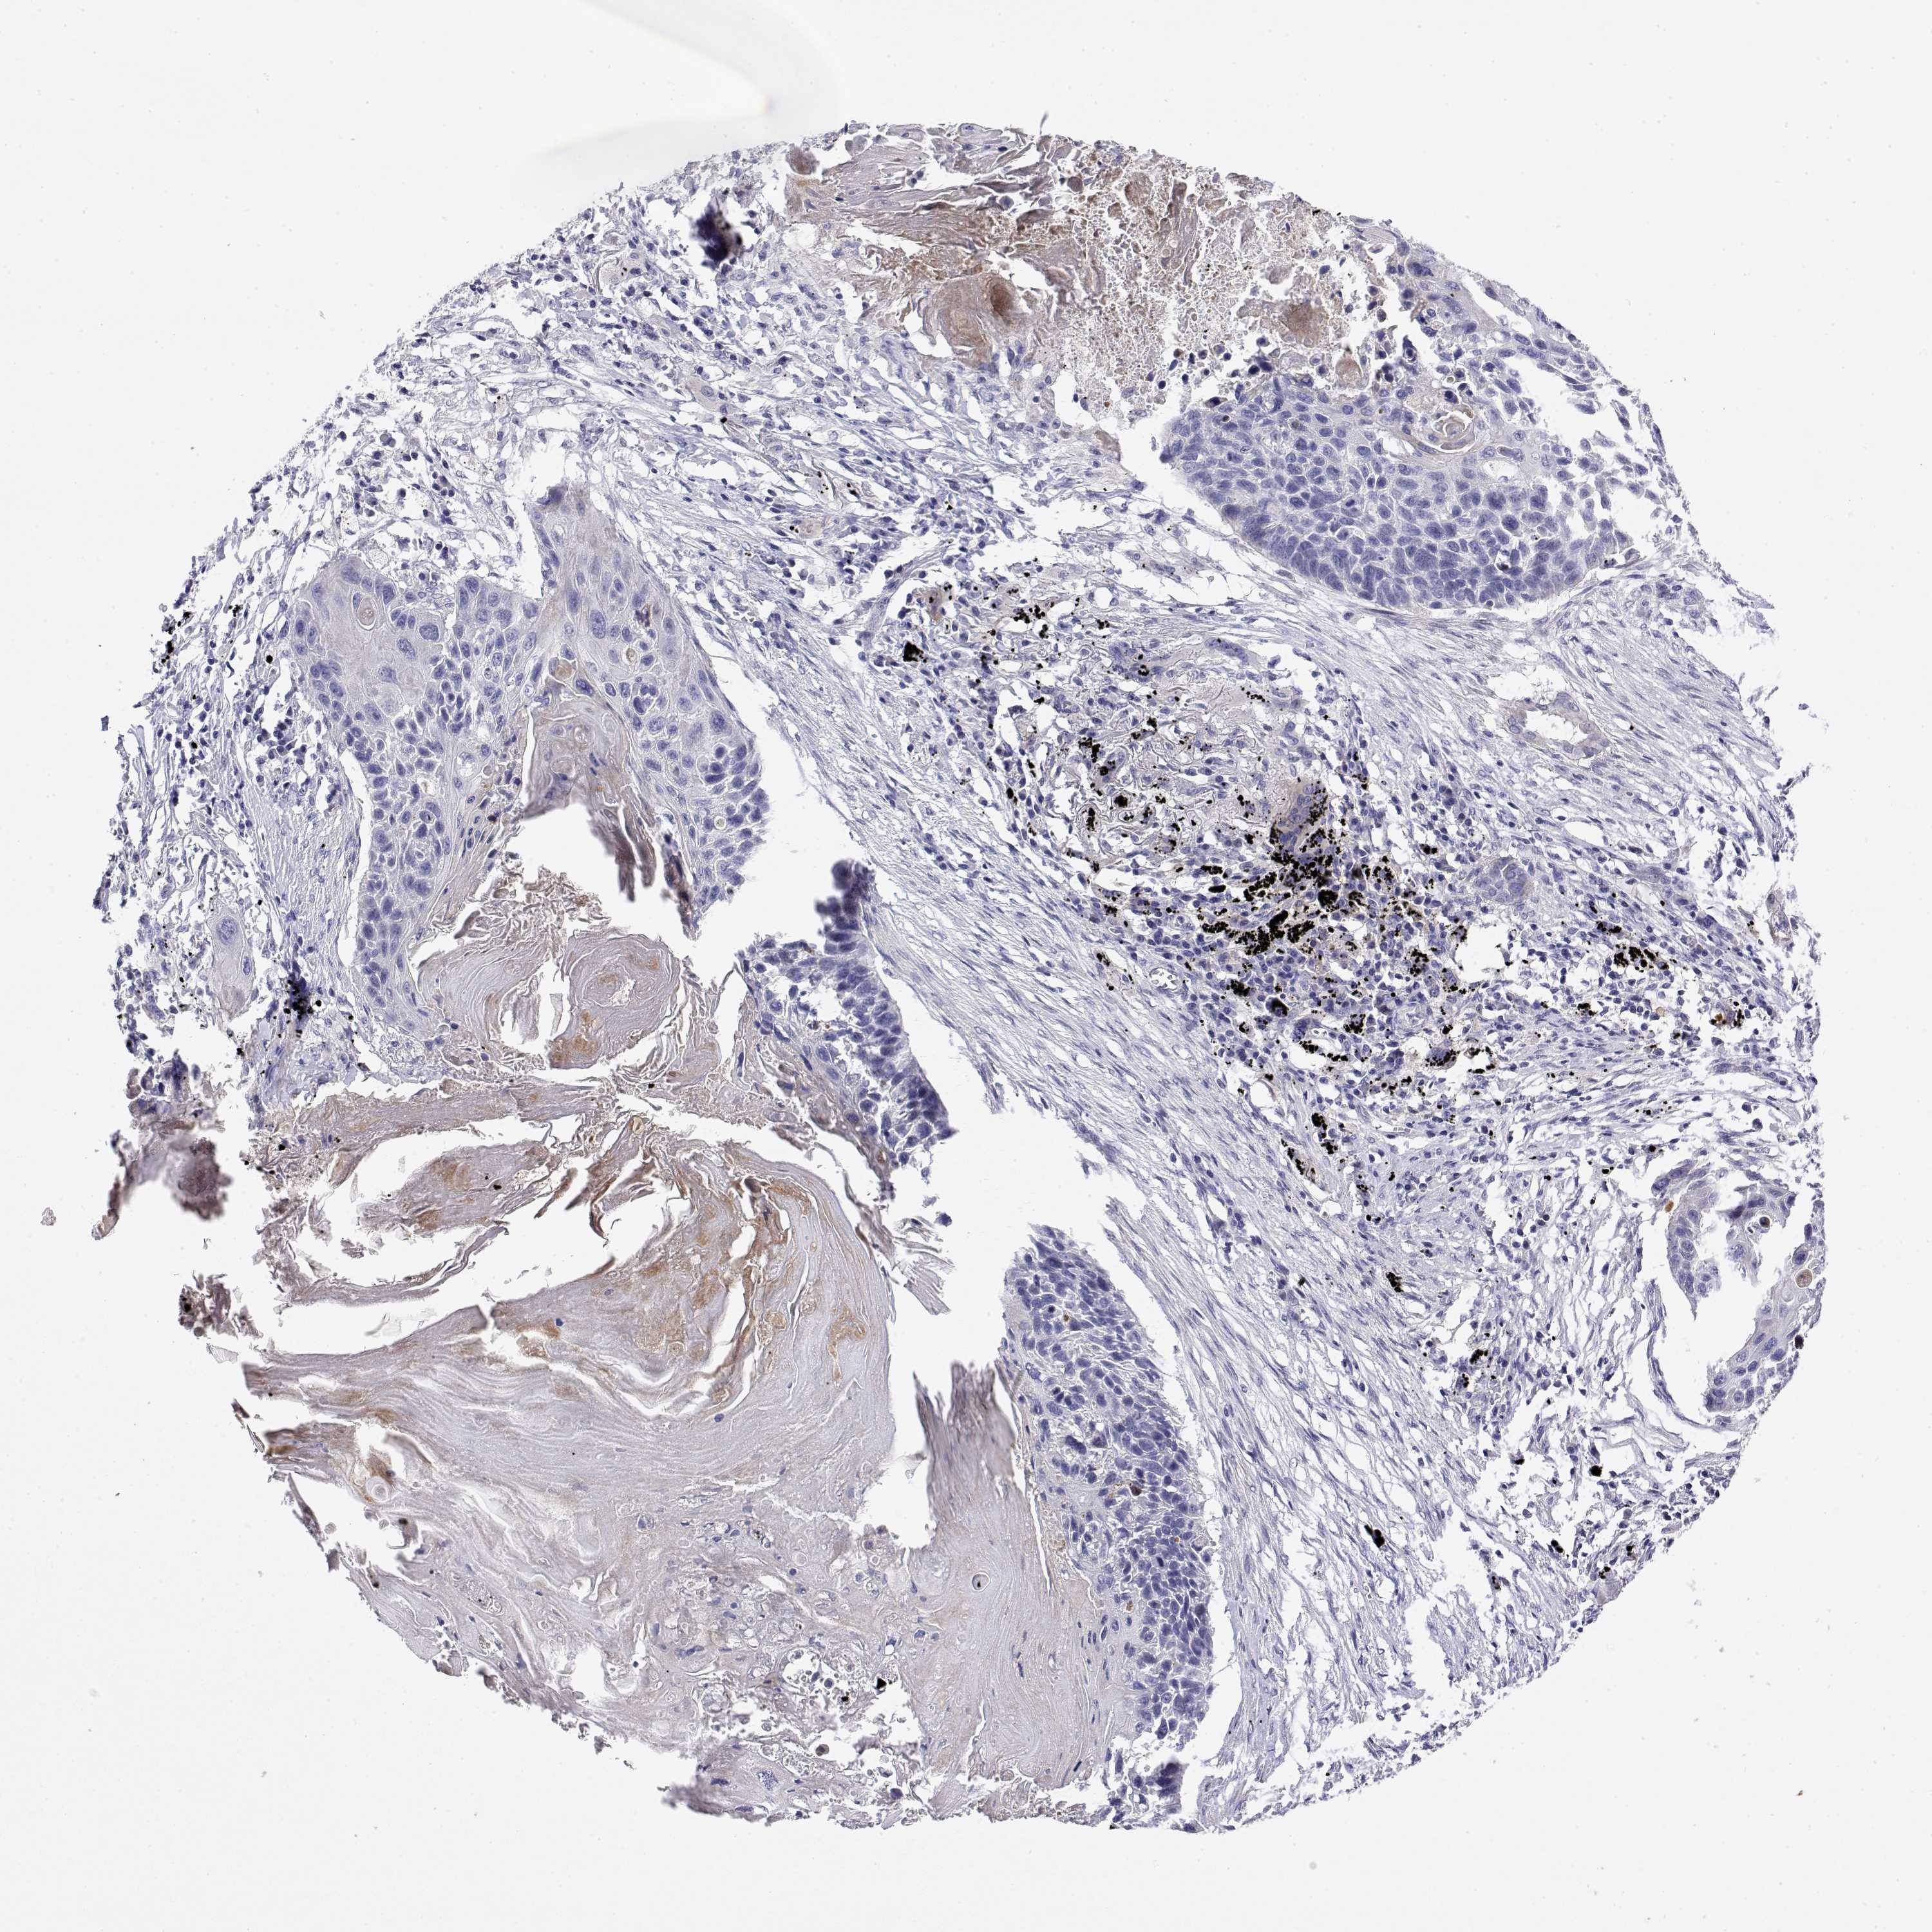

CANCER LUNG CANCER Show tissue menu

Lung cancer

Human cancer